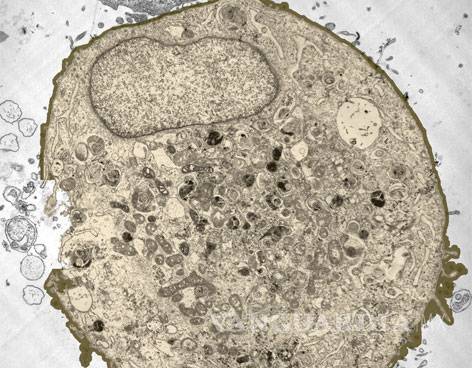

El Fondo Mundial para la Investigación del Cáncer alertó de que en los próximos años la incidencia podría aumentar de forma drástica; los casos de cáncer que se detectan cada año son ya cuatro veces más que el VIH

LONDRES, Ing. El número de casos de cáncer subió un 20 por ciento en el mundo en la última década hasta alcanzar 12 millones de nuevas detecciones al año, según divulgó hoy el Fondo Mundial para la Investigación del Cáncer (WCRF, en sus siglas en inglés) .

La organización alertó que en los próximos años la incidencia de la enfermedad podría aumentar de forma "drástica" y recalcó que los casos de cáncer que se detectan cada año son ya cuatro veces más que las infecciones por VIH (2.6 millones) y muchos se pueden prevenir.

El WCRF, que agrupa a organizaciones sin ánimo de lucro dedicadas a la investigación y la prevención del cáncer, subrayó que 2.8 millones de los casos que se detectan al año están ligados a la dieta, la actividad física y el sobrepeso.